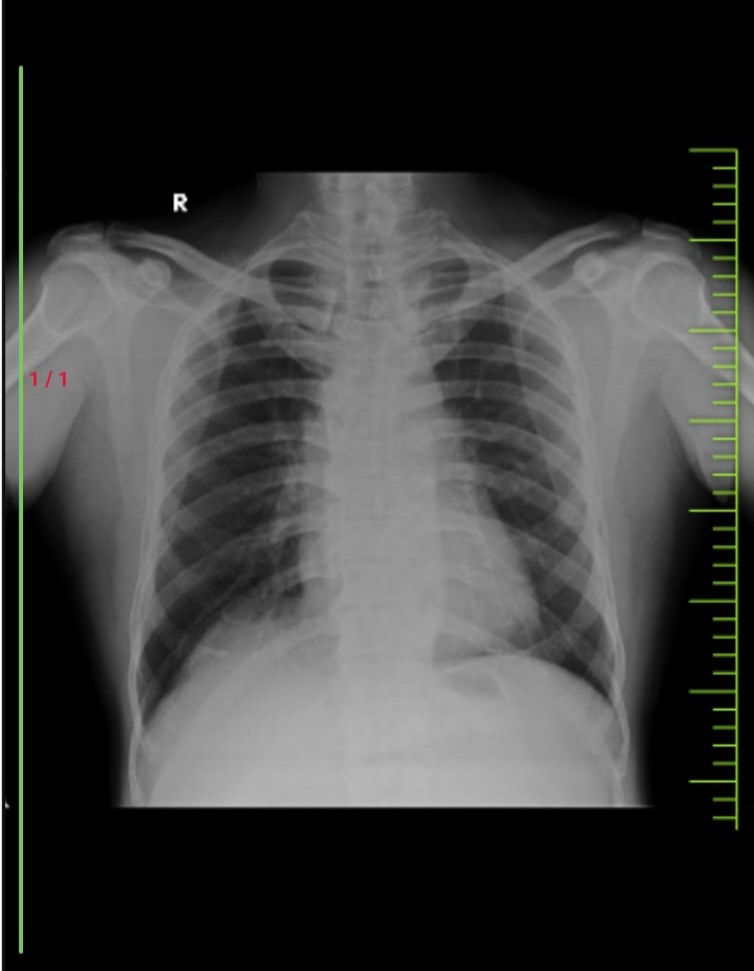

CXR PA VIEW

29/7/23